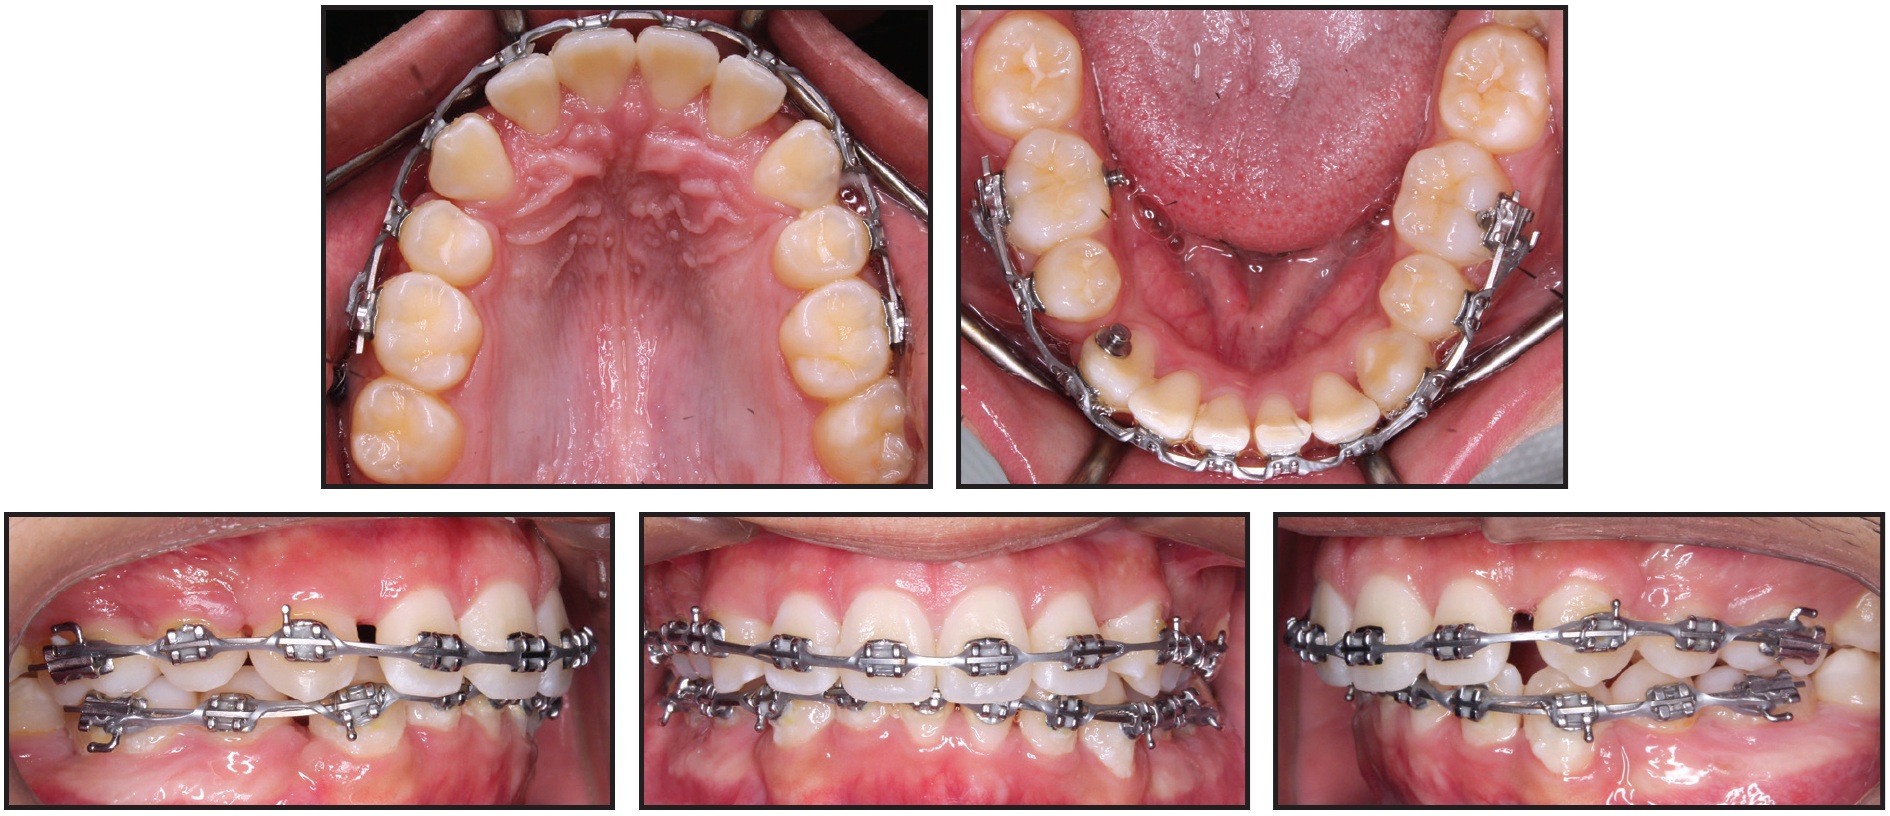

A 17-year-old male presented to the orthodontic clinic at the University of Connecticut with the chief complaint of crooked teeth. Although the patient had not had any previous orthodontic treatment, he mentioned an earlier consultation with another orthodontist, who recommended no treatment due to the condition of the dental roots. The patient had a convex soft-tissue profile with protrusive lips, a Class I molar relationship, a 50% overbite, and a 7mm overjet (Fig. 1). There was 4mm of crowding in the maxillary arch and 8mm of crowding in the mandibular arch; the mandibular dental midline was deviated 3mm to the left in relation to the facial midline.

Fig. 1 17-year-old male patient with generalized short-root anomaly, severe anterior crowding, flared upper incisors, excessive overjet, and buccal occlusion before treatment.

Fig. 1 (cont.) 17-year-old male patient with generalized short-root anomaly, severe anterior crowding, flared upper incisors, excessive overjet, and buccal occlusion before treatment.

Cephalometric analysis indicated a Class II skeletal base and a convex profile due to a prognathic maxilla. The upper incisors were proclined, and both lips were protruded in relation to the E-line (Table 1). The panoramic radiograph revealed generalized short roots, impacted lower third molars, and a missing upper right third molar.

The root/crown ratios for the first molars, premolars, canines, and upper incisors were calculated as proposed by Lind.1 The most affected teeth were the upper right and left central incisors, with root/crown ratios of .85 and .90, respectively (Table 2).

The patient was referred to his general dentist for extraction of the upper and lower first premolars. Four LOMAS* 1.5mm × 9mm, 022"/.028" slot mini-implants were placed in the maxilla, two on each side, in a vertical configuration between the first molar and second premolar. The mini-implants on each side were splinted together with a mesh of stainless steel ligature ties and composite resin. A molar tube was then bonded to each stabilized mini-implant structure to engage the base archwire (Fig. 3).

Fig. 3 Targeted mechanics for canine retraction: four mini-implants placed in maxilla and two in mandible, .022" preadjusted edgewise brackets bonded to upper and lower canines, .016" × .022" stainless steel archwires passively adapted to engage slots of canines and mini-implant brackets, and nickel titanium coil springs attached from canine brackets to mini-implants.

Two additional mini-implants were placed in the mandible, one on each side, between the first molar and second premolar.

Preadjusted .022" edgewise brackets** were bonded to the upper and lower canines, and .016" × .022" stainless steel archwires were passively adapted to engage the slots of the canine and mini-implant brackets. Canine retraction was initiated by attaching nickel titanium coil springs with 120-150g of force from the canines to the mini-implants. Six months later, some spontaneous alignment of the upper and lower incisors was observed as a result of the anterior space creation (Fig. 4). A progress panoramic radiograph indicated translation of the upper canines and lower left canine; the lower right canine was slightly tipped.

Fig. 4 After six months of canine retraction, incisor alignment spontaneously improved.

After 11 months of canine retraction, we noted additional spacing in the incisor regions and further spontaneous alignment of the upper and lower incisors, along with substantial movement of the left canines (Fig. 5). Some 3-4mm of space remained distal to the right canines.

Fig. 5 After 11 months of canine retraction, transpalatal arch soldered to upper canine bands and elastomeric chains attached from extension arms to mini-implants.

The maxillary mechanics were then modified for transverse control, with an .030" stainless steel transpalatal arch soldered to bands on the upper canines. Extension arms were soldered to the buccal surfaces of the bands so that the lines of force would pass close to the canine centers of resistance, and canine retraction was continued with elastomeric chains from the extension arms to the mini-implants. The previous mechanics were maintained in the mandibular arch.

Both upper canines and the lower left canine were fully retracted after 20 months of treatment. At this stage, both arches were bonded with .022" preadjusted edgewise brackets, and mini-implants were removed (Fig. 6).

Fig. 6 Both arches bonded with .022" preadjusted edgewise brackets, mini-implants removed, and leveling and alignment initiated after 20 months of treatment.